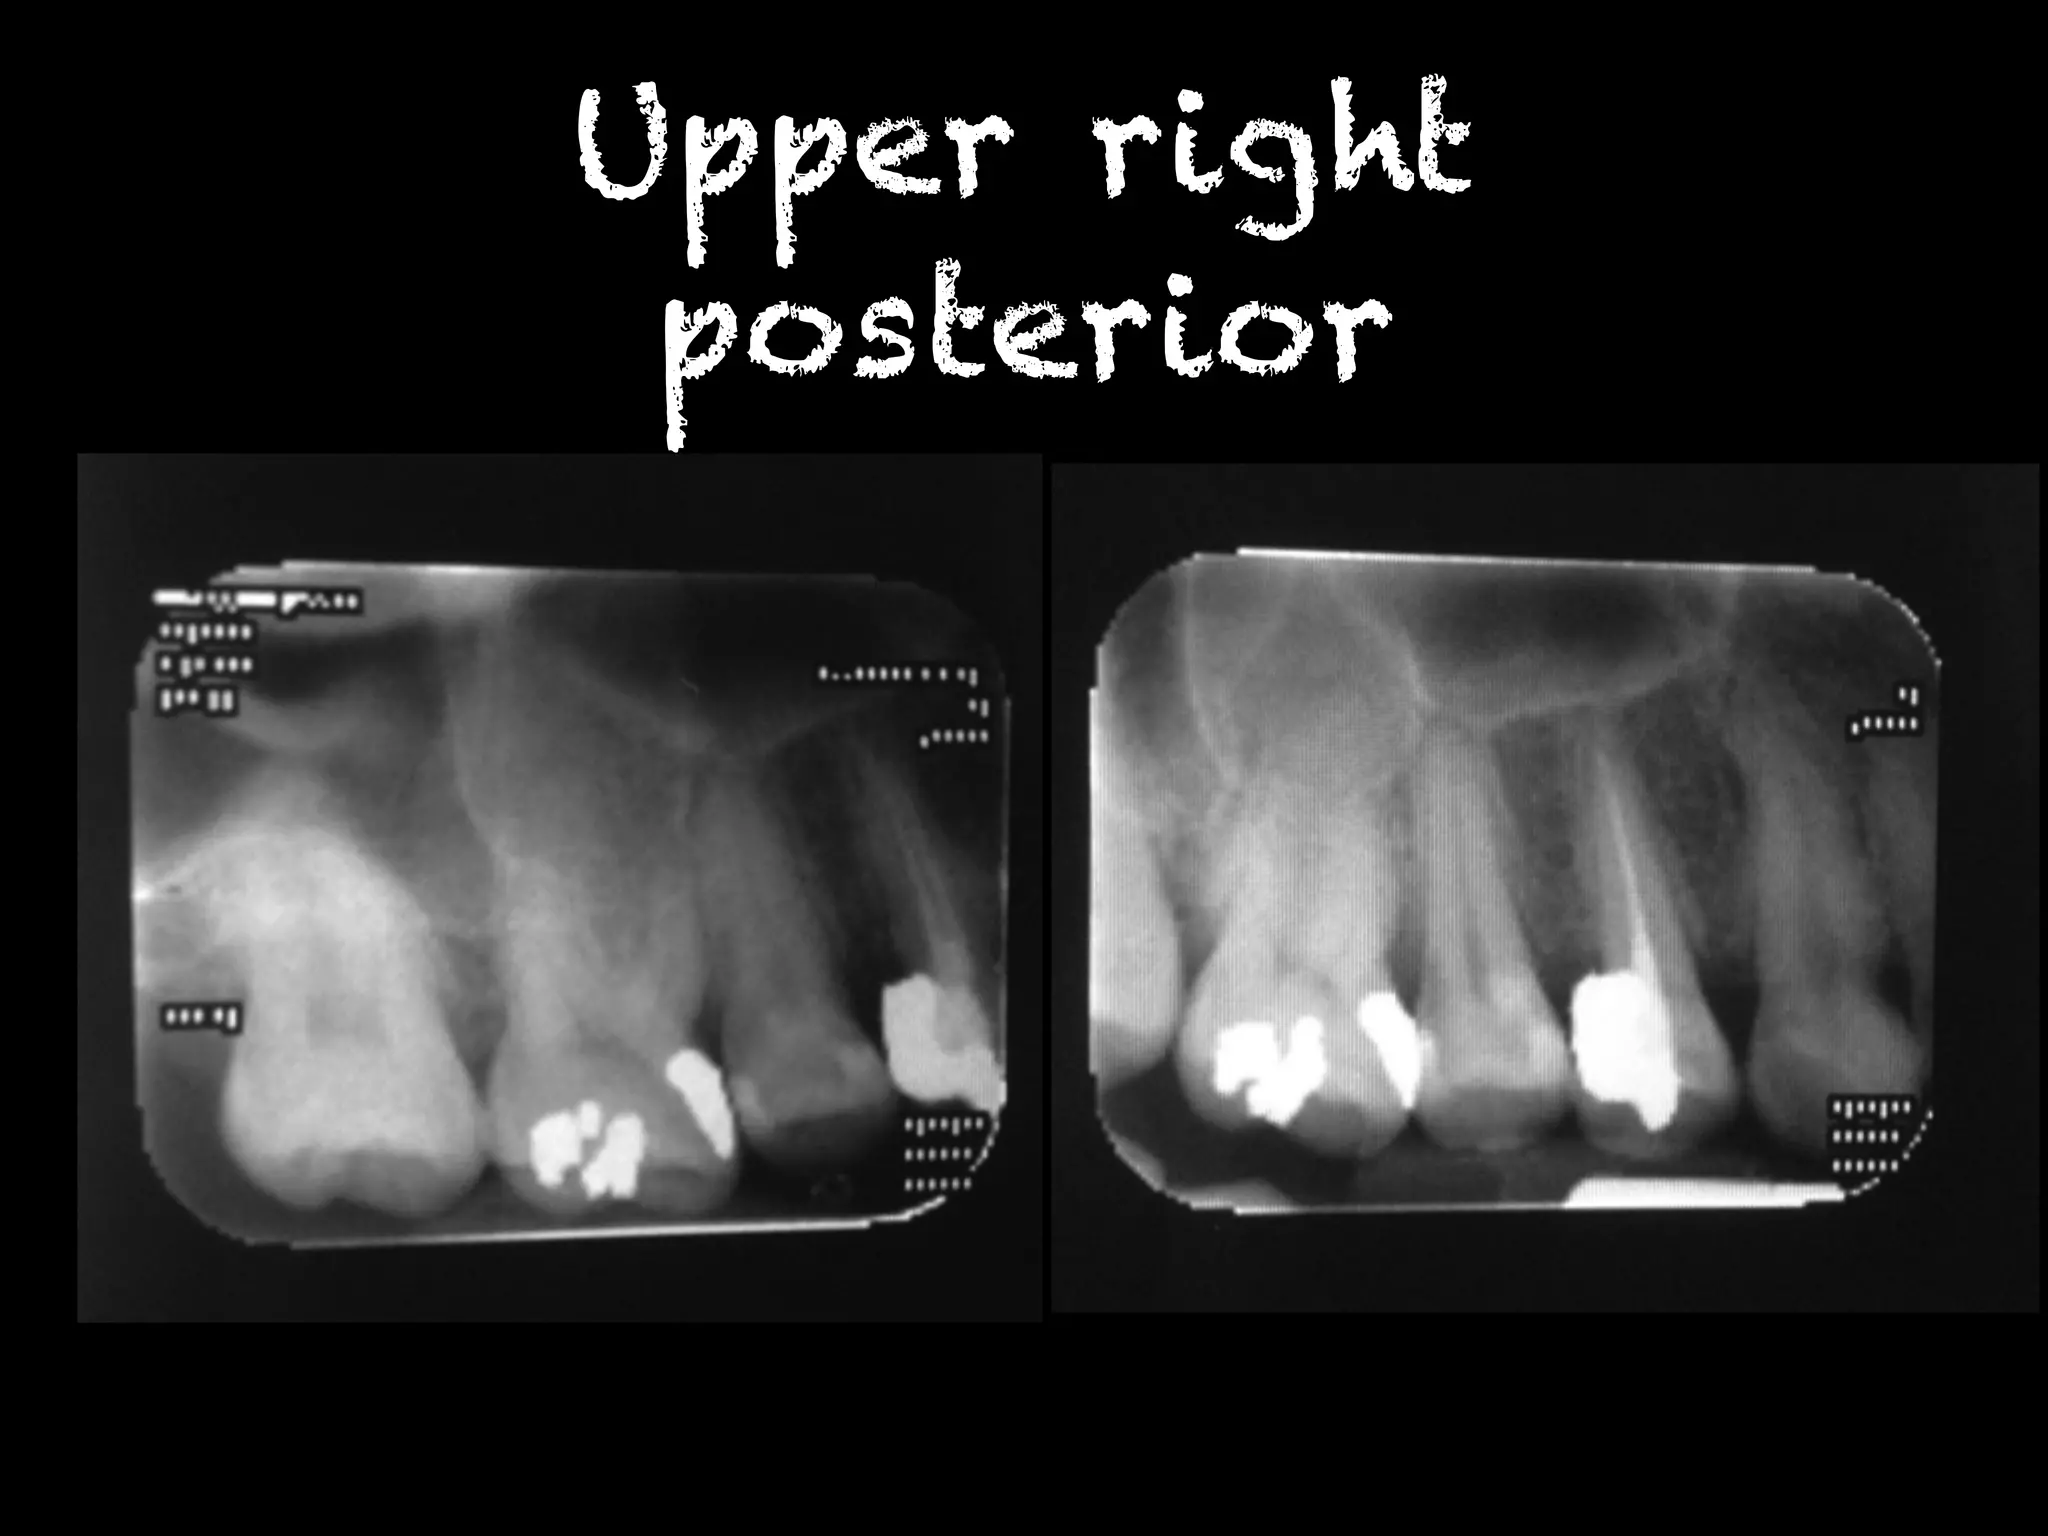

Upper right

posterior

พบรอยโรคโปร่งรังสีที่บริเวณคอฟัน ฟันซี่

12MD,13M,22MD,23M,31MD,32MD,33MD,

41MD,42MD,43MD,34MD,35MD,36MD,

48M